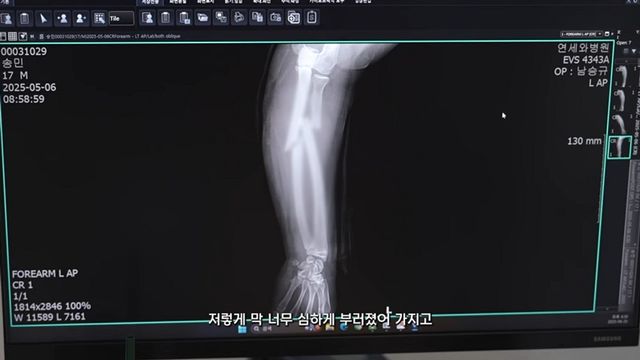

영상에서 담당 의사는 “전완부 골절이 있었따. 움직임이 많아 6주간 통깁스를 유지했다. 이제는 반깁스로 전환하지만,완전한 회복까지는 3개월 정도 더 주의가 필요하다”고 설명했다.